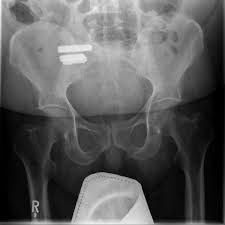

Einschlafen der Zehen gehören zu den Sensibilitätsstörungen beziehungsweise Gefühls- oder Empfindungsstörungen. Ein lumbaler Bandscheibenvorfall der nicht in Verbindung mit einer Lumbalgie oder einem Hexenschuss steht kann zu Schmerzen im. Welche Rolle spielt die Bandscheibe.

Der Faserring der untersten Bandscheiben nutzt sich ab altert und bekommt Risse durch die Gewebe aus dem Inneren der. Je nachdem welcher Nerv durch den Vorfall beeinträchtigt ist können das Kribbeln sowie andere Symptome an unterschiedlichen Stellen des Körpers auftreten. Taube Zehen re u lks Schmerzen in grossen Zehen stechen verformung zeh neben grossen Zeh blase kleinen Zeh Schmerzen kl zeh ja mache intensiv heiße Bader mit Kräutern massiere creme und ziehe nur Turnschuhe an.

Häufig ist ein Taubheitsgefühl harmlos und verschwindet nach kurzer Zeit von selbst. Die Lokalisation an welcher das Kribbeln wahrgenommen wird wird von der Höhe des Bandscheibenvorfalls maßgeblich beeinflusst. Er hat ein MRT machen lassen und festgestellt dass ich eine leichte lumbale Spondylarthrose Verschleißerscheinungen an der Wirbelsäule von. Seit heut morgen ist mein großer Zeh taub. Bin sportlich aktiv und trage schon immer passende Schuhe ernähre mich gesund und Vitamin Reich bin Asthmatiker seit meiner Geburt mit all möglichen Allagien muss regelmäßig Medikamente nehmen. 6 Gründe warum die Zehen plötzlich taub werden. Je nachdem welcher Nerv durch den Vorfall beeinträchtigt ist können das Kribbeln sowie andere Symptome an unterschiedlichen Stellen des Körpers auftreten. Meistens sind beide Füße betroffen manchmal treten die Beschwerden auch nur einseitig auf. Dazu kommt dass ich meinen unteren Rücken spüre habe aber keinerlei Schmerzen.